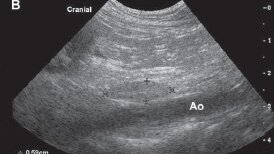

Ультразвуковое исследование лимфоузлов брюшной полости

В настоящее время абдоминальные лимфатические узлы входят в рутинное ультразвуковое исследование брюшной полости. Детальное описание проводится только в случае выявления патологических изменений. В норме лимфатические узлы имеют четкие контуры, овальную или веретенообразную форму, однородную структуру, эхогенность близкая к окружающим тканям – т.е. изоэхогенная или умеренно гипоэхогенная. Размеры лимфатических узлов достаточно вариабельны, зависит от размера животного. Большее значение имеет соотношение короткой и длинной осей; оно не должно превышать < 0,5...